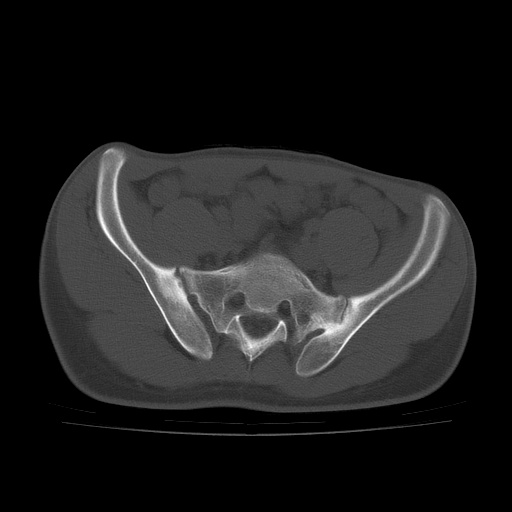

患者男性,18岁 腰腿痛1年  骶髂关节改变本人考虑强直性脊柱炎。

两侧骶髂关节骨质破坏,关节面毛糙,符合强直性脊柱炎骶髂关节改变。

符合强直性脊柱炎,虫蚀样骨质破坏。

两侧骶髂关节骨质破坏,关节面呈锯齿样改变关节间隙变窄,考虑强真性脊柱炎

双侧骶髂关节关节间隙变窄,边缘毛糙,关节面硬化,可见囊变!符合强直变现!

两侧骶髂关节骨质破坏以髂骨为主,间隙变窄,强直性脊柱炎